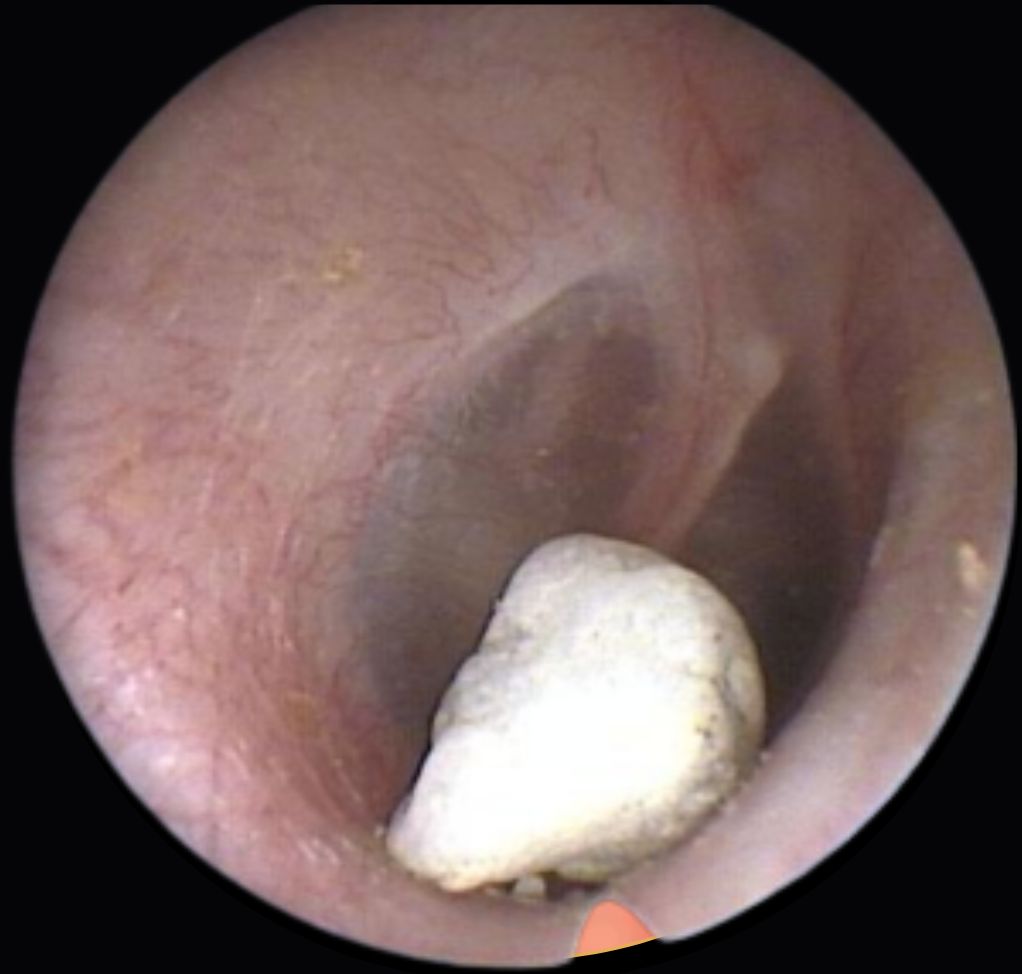

Signs of ear canal and eardrum problems

Look at these pictures of the inside of the ear. Do they look healthy?

No, the ear canal is blocked with a foreign body.